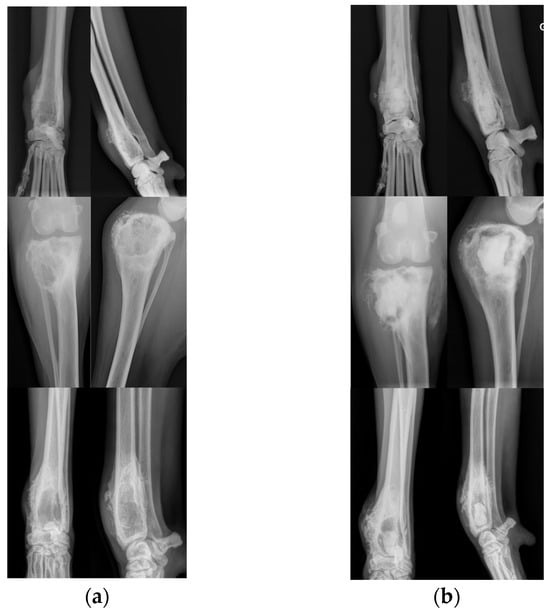

Radiographs of three cases are presented in Figure 1.

Postoperative radiographs showed the presence of the calcium phosphate cement in the injected bone (X-rays of representative cases of injection are presented in Figure 1). The persistence of the product was observed in all dogs without any major macroscopic modification throughout the study period, demonstrating the stability of the cement inside the tumoral cavity and supporting the beneficial mechanical effects expected with the cementoplasty procedure. Radiographic evaluation also aimed to identify the occurrence of pathologic fracture. During the study follow-up, only 1 animal, with a distal radius OSA, experienced a pathological fracture. Nevertheless, the fracture did not occur at the tumor localization but on the ipsilateral ulna.

Figure 1. Pre- and post-operative radiographs of distal radius (dog 1 and 9) and proximal (dog 4) OSA treated by cementoplasty procedure. Cranio-caudal and latero-medial views of the cases before (a) and directly after (b) the injection of the calcium phosphate cement.